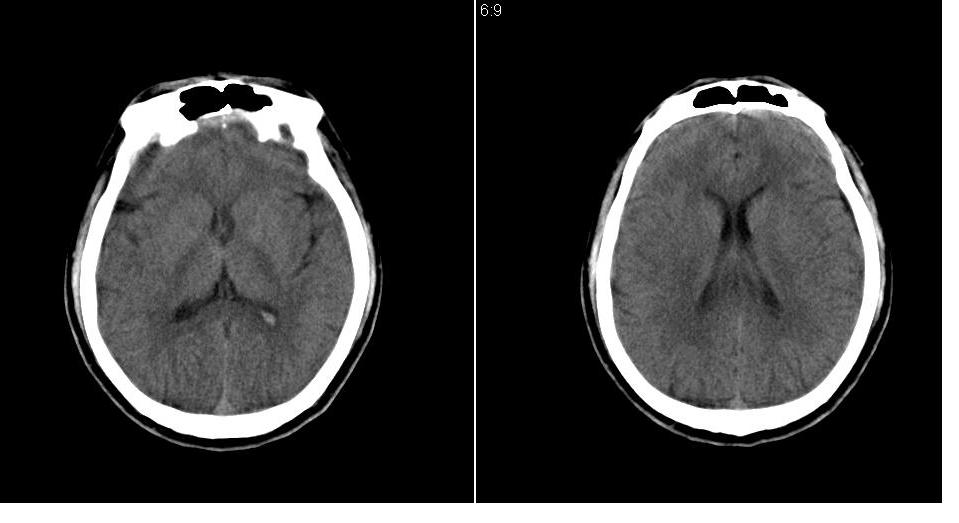

男 32岁,外伤。

大枕大池、左侧外侧裂池区蛛网膜囊肿

大枕大池、左侧外侧裂池区蛛网膜囊肿 。目前只能看到这些。

支持左侧中颅窝蛛网膜囊肿。

大枕大池、左侧颅中窝蛛网膜囊肿.